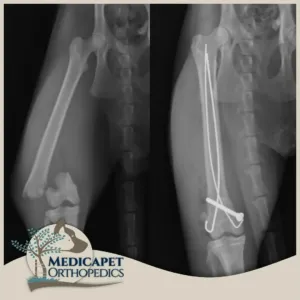

Intrameduller Pin Uygulamaları

“Intrameduller” terimi “kemik içi” anlamına gelmektedir. Bu yöntemde kemiğin medullasına, yani iç kısmına yerleştirilen vidalı ya da vidasız pinlerle kemiği eski pozisyonuna getiriip sabitlemeyi amaçlıyoruz. İntrameduller pin uygulamalarını kemiğin rotasyon ihtimalinin olmadığı durumlarda kullanıyor. Bu ameliyatlarda bazen kemiği dışarıdan da serklaj telleri ile destekliyoruz. İntrameduller pinler iyileşmeyi takiben çıkarılabiliyor ya da iyileşen kemik içerisinde ömür boyu bırakılabiliyor. Fakat büyüme çağında olan hastalarda pinin lokasyonuna göre iyileşmeyi takiben pinin çıkarılmasını öneriyoruz. Ayrıca bazı kompleks kırıklarda intrameduller pinleri plaklarla birlikte de uygulayabiliyoruz.